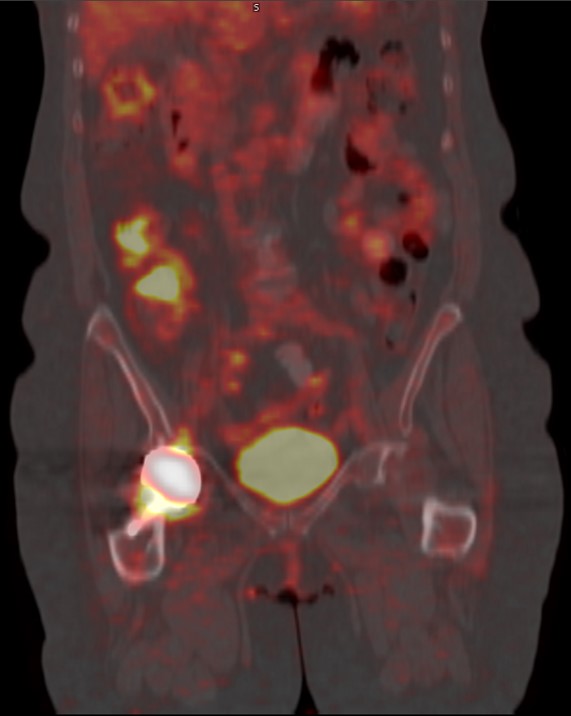

A) 50 year-old women with history of osteosarcoma of left distal femur status post resection and limb sparing prosthesis. B) Left to right, top to bottom, axial bone window CT and FDG PET, fused axial and coronal images of the lower thigh demonstrate the prosthesis within the distal left femur producing streak artifact and photopenia on the PET images. |

60 year-old women with right hip hemiarthoplasty. Axial CT bone window image (5A) demonstrates right hip prosthesis. |

| Axial bone window (5B) NON-attenuation corrected (NAC) and attenuation corrected (AC) FDG PET (5C), fused axial and coronal (5D, 5E), images of the pelvis demonstrate the right femoral prosthesis with photopenia in the region of prosthesis. Periprosthetic FDG uptake is seen on AC and fused images and is minimally seen on the NAC image, consistent with attenuation correction artifact. |